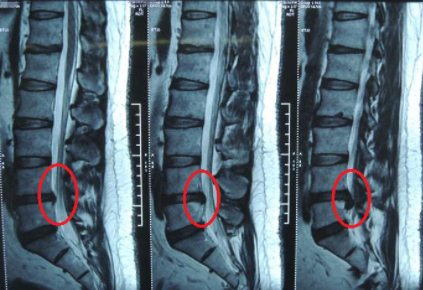

当时去医院后先是给医生描述症状,之后医生就让我去做一个ct,当时等了好久才做上,结果一出来就拿去给医生看,当时他就说是腰椎间盘突出还伴有右侧神经受压,所以才会出现强烈的疼痛感。